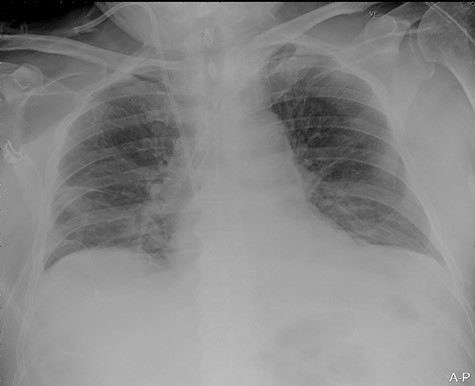

Our surgical team was contacted after 4 h, as the pleural fluid had become grossly haemorrhagic. A CXR showed haemothorax (Fig. 2). Upon clinical deterioration, the patient was intubated, and a 24Ch chest tube was introduced. Approximately, 500 ml of blood was immediately drained, followed by 300 ml during the first 30 min. ICA laceration was suspected. Despite transfusion of red blood cells and plasma and infusion of noradrenaline, the patient remained circulatory unstable. A new CXR showed massive haemothorax despite drainage (Fig. 3). The patient was now utterly haemodynamically unstable and not suited for transportation. As there are no thoracic surgeons or interventional radiologists in our hospital, the general surgeons decided to take him to the operating theatre. A wide anterolateral right thoracotomy was performed with patient lying in left lateral decubitus position. The right pleural cavity was full of fresh and coagulated blood. The pulsating bleeding was seen coming from the posterolateral, caudal chest wall, but the exact site deep down in the sharp costophrenic angle could not be localized and was inaccessible for any surgical haemostatic manoeuvre.

Portable chest X-ray in half-upright position showing massive haemothorax despite chest tube.